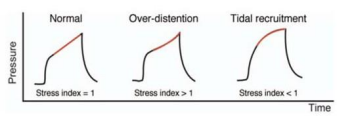

O gráfico apresentado mostra a mensuração de um parâmetro facilmente obtido beira leito nos pacientes em ventilação mecânica.

O gráfico apresentado mostra a mensuração de um parâmetro facilmente obtido beira leito nos pacientes em ventilação mecânica.